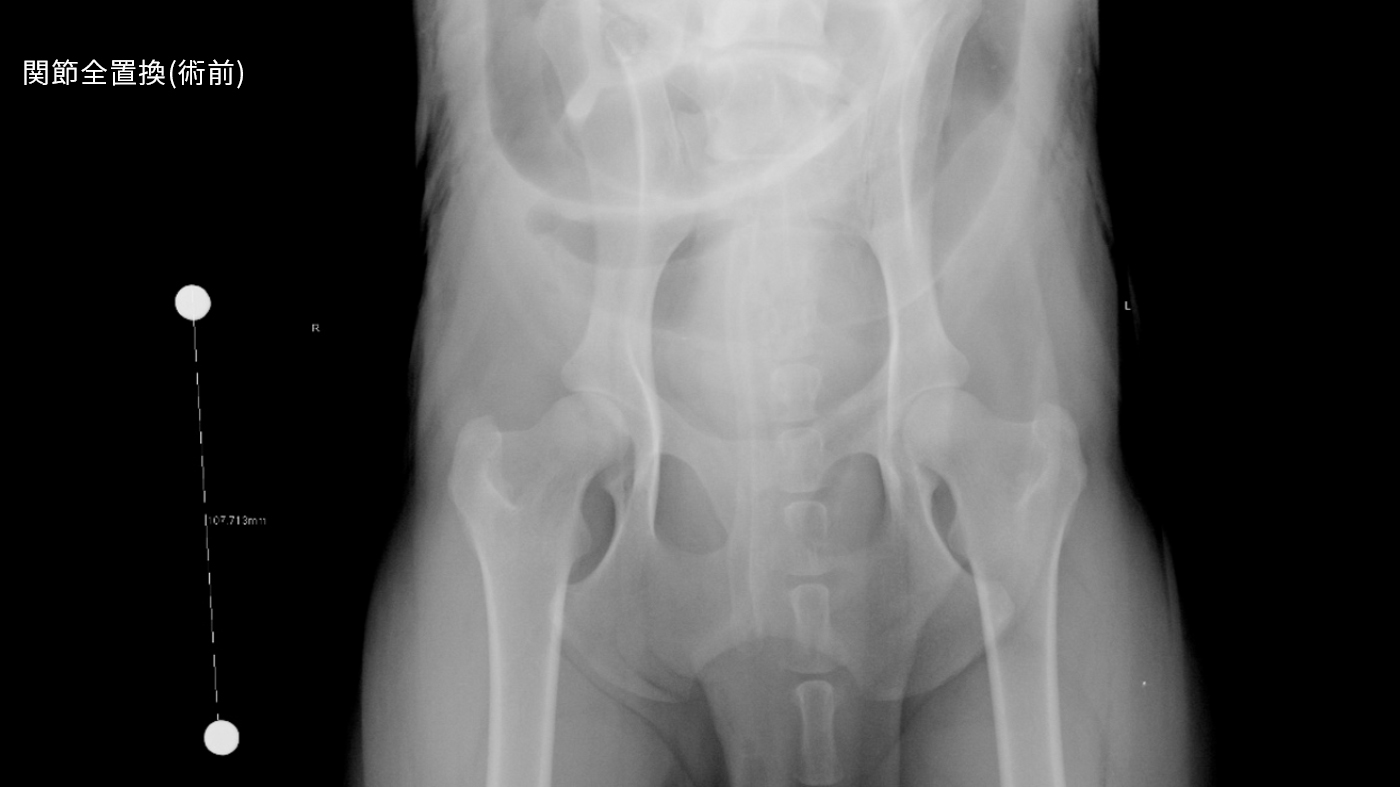

難治性手術症例;股関節全置換術(人工関節)、骨変形に対する矯正骨切り、骨折治療後の癒合不全、前十字靭帯断裂(TPLO,CBLO,mCTWO,mCBLO,頸部椎体固定、胸腰部椎体固定、環軸不安定症固定術)

「Zürich Mini Cementless Hip Repを用いて

股関節疾患を治療した小型犬の6 例の短期成績」

Zurich Mini Cementless Total Hip Arthroplasty in less than 4 kg body weight tiny breed dogs: long term Outcome in 10 Cases, ACVS Surgery

Summit, Oct. 2024 他多数